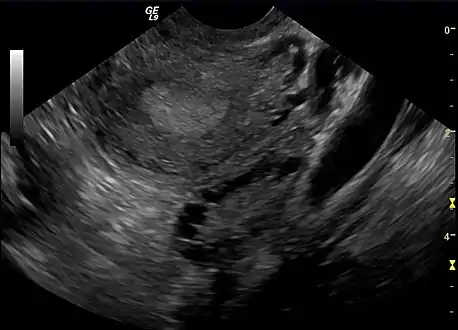

| A polycystic ovary | |

The syndrome acquired its most widely used name due to the common sign on ultrasound examination of multiple (poly) ovarian cysts. These "cysts" are in fact immature ovarian follicles. The follicles have developed from primordial follicles, but this development has stopped ("arrested") at an early stage, due to the disturbed ovarian function. The follicles may be oriented along the ovarian periphery, appearing as a 'string of pearls' on ultrasound examination.[86]

Not every person with PCOS has polycystic ovaries (PCO), nor does everyone with ovarian cysts have PCOS; although a pelvic ultrasound is a major diagnostic tool, it is not the only one.[91] The diagnosis is fairly straightforward using the Rotterdam criteria, even when the syndrome is associated with a wide range of symptoms.[92]

Transvaginal ultrasound scan of polycystic ovary

Polycystic ovary as seen on sonography

- Gynecologic ultrasonography, specifically looking for small ovarian follicles. These are believed to be the result of disturbed ovarian function with failed ovulation, reflected by the infrequent or absent menstruation that is typical of the condition. In a normal menstrual cycle, one egg is released from a dominant follicle – in essence, a cyst that bursts to release the egg. After ovulation, the follicle remnant is transformed into a progesterone-producing corpus luteum, which shrinks and disappears after approximately 12–14 days. In PCOS, there is a so-called "follicular arrest"; i.e., several follicles develop to a size of 5–7 mm, but not further. No single follicle reaches the preovulatory size (16 mm or more). According to the Rotterdam criteria, which are widely used for diagnosis of PCOS,[10] 12 or more small follicles should be seen in a suspect ovary on ultrasound examination.[21] More recent research suggests that there should be at least 25 follicles in an ovary to designate it as having polycystic ovarian morphology (PCOM) in women aged 18–35 years.[95] The follicles may be oriented in the periphery, giving the appearance of a 'string of pearls'.[96] If a high-resolution transvaginal ultrasonography machine is not available, an ovarian volume of at least 10 ml is regarded as an acceptable definition of having polycystic ovarian morphology. rather than follicle count.[95]

Ultrasound findings in PCOS include enlarged ovaries with peripheral follicles in a "string of pearls" configuration.